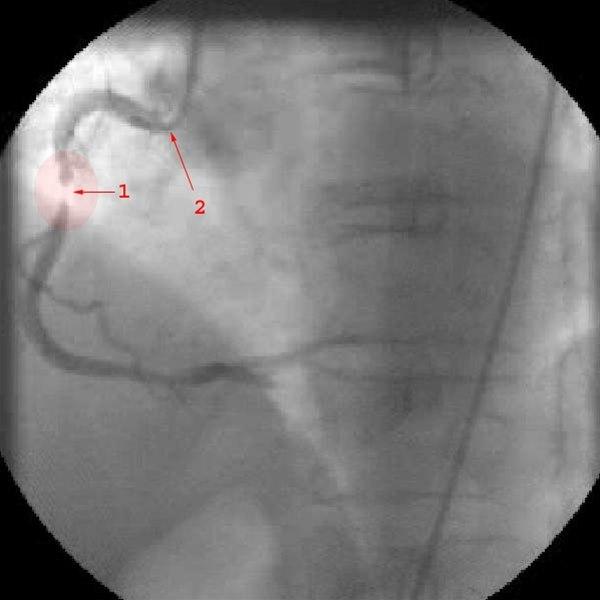

Diagnosen bygger i all hovedsak på sykehistorien. Det vil si de symptomer og tegn som du selv merker. Ved raskt økende brystsmerter av den beskrevne typen bør du ta kontakt med lege snarest. Som regel vil det være aktuelt å legge deg inn på sykehus til observasjon og behandling. EKG og blodprøver vil avklare om det er angina eller om det er oppstått et akutt hjerteinfarkt. I de fleste tilfeller vil det være aktuelt å ta bilder av koronararteriene ved en hjertekateterisering (se video nedenfor).

Tidlig etter innkomsten vil legene vurdere om du bør få utført utblokking av koronararterien(e) som er blitt trange - inngrepet kalles perkutan koronar intervensjon (PCI). Helst vil man gjøre det innen 12-24 timer.

Ved PCI føres et kateter inn i den trange blodåren, åren vides ut og i de fleste tilfeller setter man inn en stent. Stent er en type armering som skal forebygge at blodåren lukker seg igjen. Andre ganger kan det bli nødvendig med en åpen hjerteoperasjon der man syr inn en ny blodåre forbi den eller de årene som er trange (bypass-operasjon).